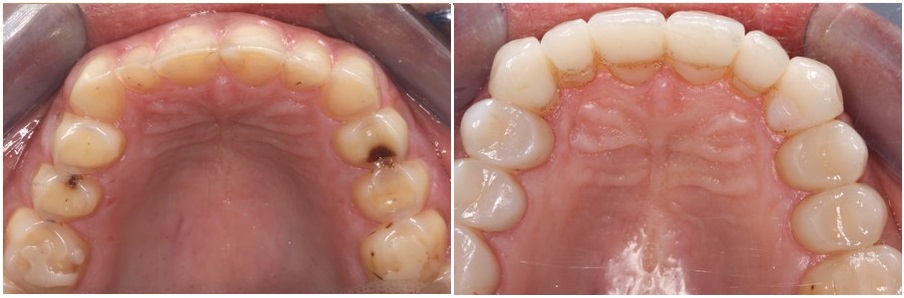

Στις φωτογραφίες που ακολουθούν βλέπουμε την άνω και την κάτω γνάθο γνάθο πριν και μετά την ολοκλήρωση των αποκαταστάσεων.

Στα περισσότερα δόντια είχε χαθεί η αδαμαντίνη και σημαντική ποσότητα από την οδοντίνη. Τα δόντια είχαν χάσει τα μορφολογικά τους χαρακτηριστικά, ενώ το ύψος του κάτω τριτημορίου του προσώπου είχε χαθεί.

Η διάβρωση είχε προσβάλλει όλα σχεδόν τα δόντια της άνω και κάτω γνάθου.

Το αποτέλεσμα είναι εντυπωσιακό. Η ασθενής μας χαμογελά με αυτοπεποίθηση ενώ τα δόντια δεν είναι πια ευαίσθητα στα θερμικά ερεθίσματα.